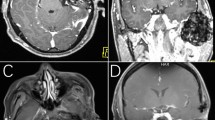

A 52-year-old man suffered from a 10-month history of tightness in his right ear. A mass lesion that protruded from the external auditory canal was discerned. CT scan revealed bone destruction of the right mandibular condyle and a soft-tissue mass measuring 2.0 × 1.8 cm with calcification, which had invaded the temporal bone and temporomandibular joint (Figure 1). After open biopsy, tumor resection was carried out. Follow-up magnetic resonance imaging (MRI) 11 months after surgery revealed no tumor recurrence.

A 67-year-old man suffered from a 3-month history of pain in the left ear and swelling of the left cheek. MRI demonstrated a mass lesion, which was destroying the left temporal bone, involving the middle fossa and the temporomandibular joint. Angiography revealed a hypervascular mass. Following open biopsy, tumor resection was performed. Currently, the patient remains free of tumor recurrence 7 years and 3 months after the surgery.

A 52-year-old woman complained of a 3-year history of right coxalgia. She had also noticed a mass lesion in her right groin about 6 months earlier. Plain radiography showed bone erosion in the right femoral neck. MRI revealed a tumor measuring 3.0 × 2.0 cm with fluid beneath the femoral neck, which showed low intensity on T1-weighted images (WI) and low intensity on T2-WI (Figure 2). The preoperative clinical diagnosis was pigmented villonodular synovitis and the patient underwent tumor resection. Postoperative imaging 2 years after the surgery revealed no recurrence.